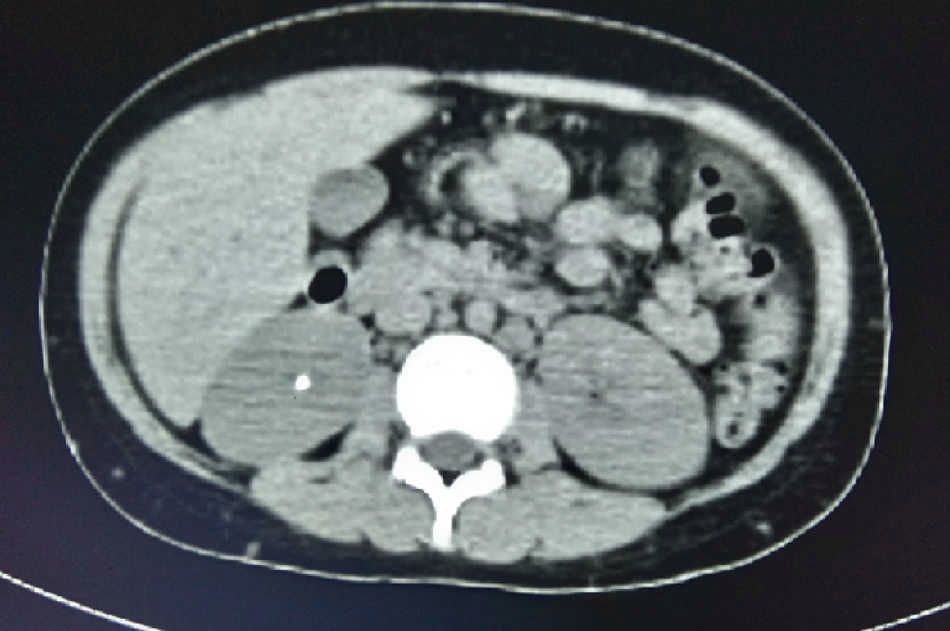

Se inició tratamiento con prednisona 2 mg/kg/día e hidroclorotiazida 1.2 mg/kg/día, con lo cual se observó mejoría clínica de su estado general, con remisión de la hepatomegalia y la esplenomegalia, del eritema nodoso, así como de las adenopatías y de la masa testicular. Posteriormente, desaparecieron las adenopatías mediastinales y los infiltrados pulmonares (Fig. 10).

Cuatro meses después el paciente estaba asintomático, había recuperado 15 kg de peso y se había incorporado a sus actividades escolares. La tomografía de abdomen sin adenopatías retroperitoneales. De igual forma, el ultrasonido renal no mostró lesiones focales ni dilatación de sistemas colectores y sin evidencia de litiasis renal. Se repitieron las pruebas de espirometría y pletismografía que fueron compatibles con patrón normal. Los exámenes de laboratorio mostraron calcio sérico 9.0 mg/dl, fósforo 5.8 mg/dl, creatinina 0.8 mg/dl, ácido úrico 6.2 mg/dl y calciuria en orina de 24 horas 0.93 mg/kg/día. Así mismo, la determinación de control de la ECA fue de 71 U/l, por lo que se consideró que la sarcoidosis se encontraba en remisión.

Inicialmente presentaba insuficiencia renal aguda, que remitió sin terapia de reemplazo renal ya que no tuvo criterios para diálisis. Además, se comprobó hipercalciuria hipercalcémica acompañada de hiperfosfaturia y disminución de la reabsorción tubular de fosfatos, que se expresó en forma de oxalato de calcio y fosfato de calcio, lo cual le ocasionó enfermedad litiásica renal. Si bien la presentación clínica de dolor cólico agudo es poco habitual en la urolitiasis de los niños, este paciente se presentó con dolor en flanco derecho acompañado de hematuria microscópica. Como parte del manejo médico se proporcionó tratamiento con hidroclorotiazida, con el fin de reducir la excreción renal de calcio y disminuir la formación de litiasis cálcica de oxalato y fosfato de calcio, logrando la remisión de la hipercalciuria, la expulsión del cálculo renal, y por lo tanto la disminución del riesgo litogénico66 67 68 69 70 71 72 (Fig. 11).

Figura 11 Tomografía abdominal posterior al tratamiento, donde se observa la remisión de las adenopatías retroperitoneales, y desaparición del cálculo renal derecho.